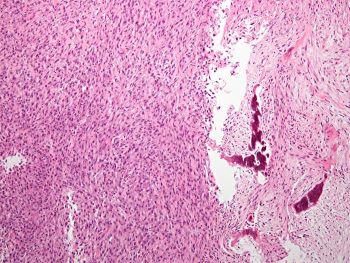

Sections show a spindle cell sarcoma with some small associated spicules of bone. Close examination of the spindle cell areas reveals an interstitial eosinophilic material that is consistent with osteoid. The immunostain provided is for SatB2 a sensitive but not specific marker of osteoblastic differentiation. The negative stains essentially exclude solitary fibrous tumor and biphenotypic sinonasal sarcoma. This tumor extended from the maxilla to the orbital floor. Osteosarcomas of the head and neck represent less than 10% of total osteosarcomas and most often arise from the mandible and maxilla. The main prognostic factor for these tumors is the margin status as they often recur locally.